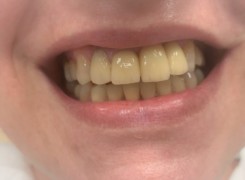

Pan Ryszard trafił do Naszego Gabinetu z jasno sprecyzowanym oczekiwaniem. Miał 84 lata i chciał odzyskać możliwość swobodnego spożywania posiłków oraz poprawienia sobie komfortu życia a także prosił aby przywrócić mu piękny uśmiech jakim cieszył się przed laty. Już na początku pierwszej rozmowy zastrzegł, że interesuje go wyłączenie rozwiązanie uzupełnieniem protetycznym stałym. Nie miał zamiaru użytkować żadnych protez ruchomych. Mając na uwadze powyższe wykonaliśmy Panu Ryszardowi zdjęcie pantomograficzne oraz badanie tomograficzne szczęki i żuchwy na postawie których zapanowywaliśmy Pacjentowi optymalne rozwiązanie – stałe uzupełnienie protetyczne w postaci 28 koron cyrkonowych zamontowanych do dwóch belek cyrkonowych które będą przymocowane do 16 implantów w konfiguracji 8 wszczepów w szczęcie 8 w żuchwie. Po omówieniu powyższego planu przystąpiliśmy do Wspólnej pracy której efekty w poszczególnych etapach prezentujemy poniżej.